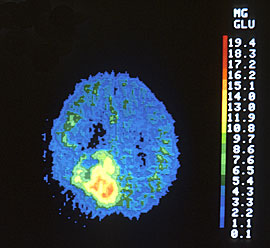

Radio-active glucose is injected in patients. The Positron Emission

Tomography (PET) scan tool is sensible to radio-active material. Since

cancer cell will consume 18 to 19 times more glucose than normal cells,

they will accumulate more radio-active material as illustrated in the

picture below.

Shown in the left is a

Positron Emission Tomography (PET) scan of a 62 year

old man with a brain tumour. The

irregular bright yellow and orange area in the lower left portion of

the brain indicates the location of the tumour,

which metabolizes glucose faster than normal cells.